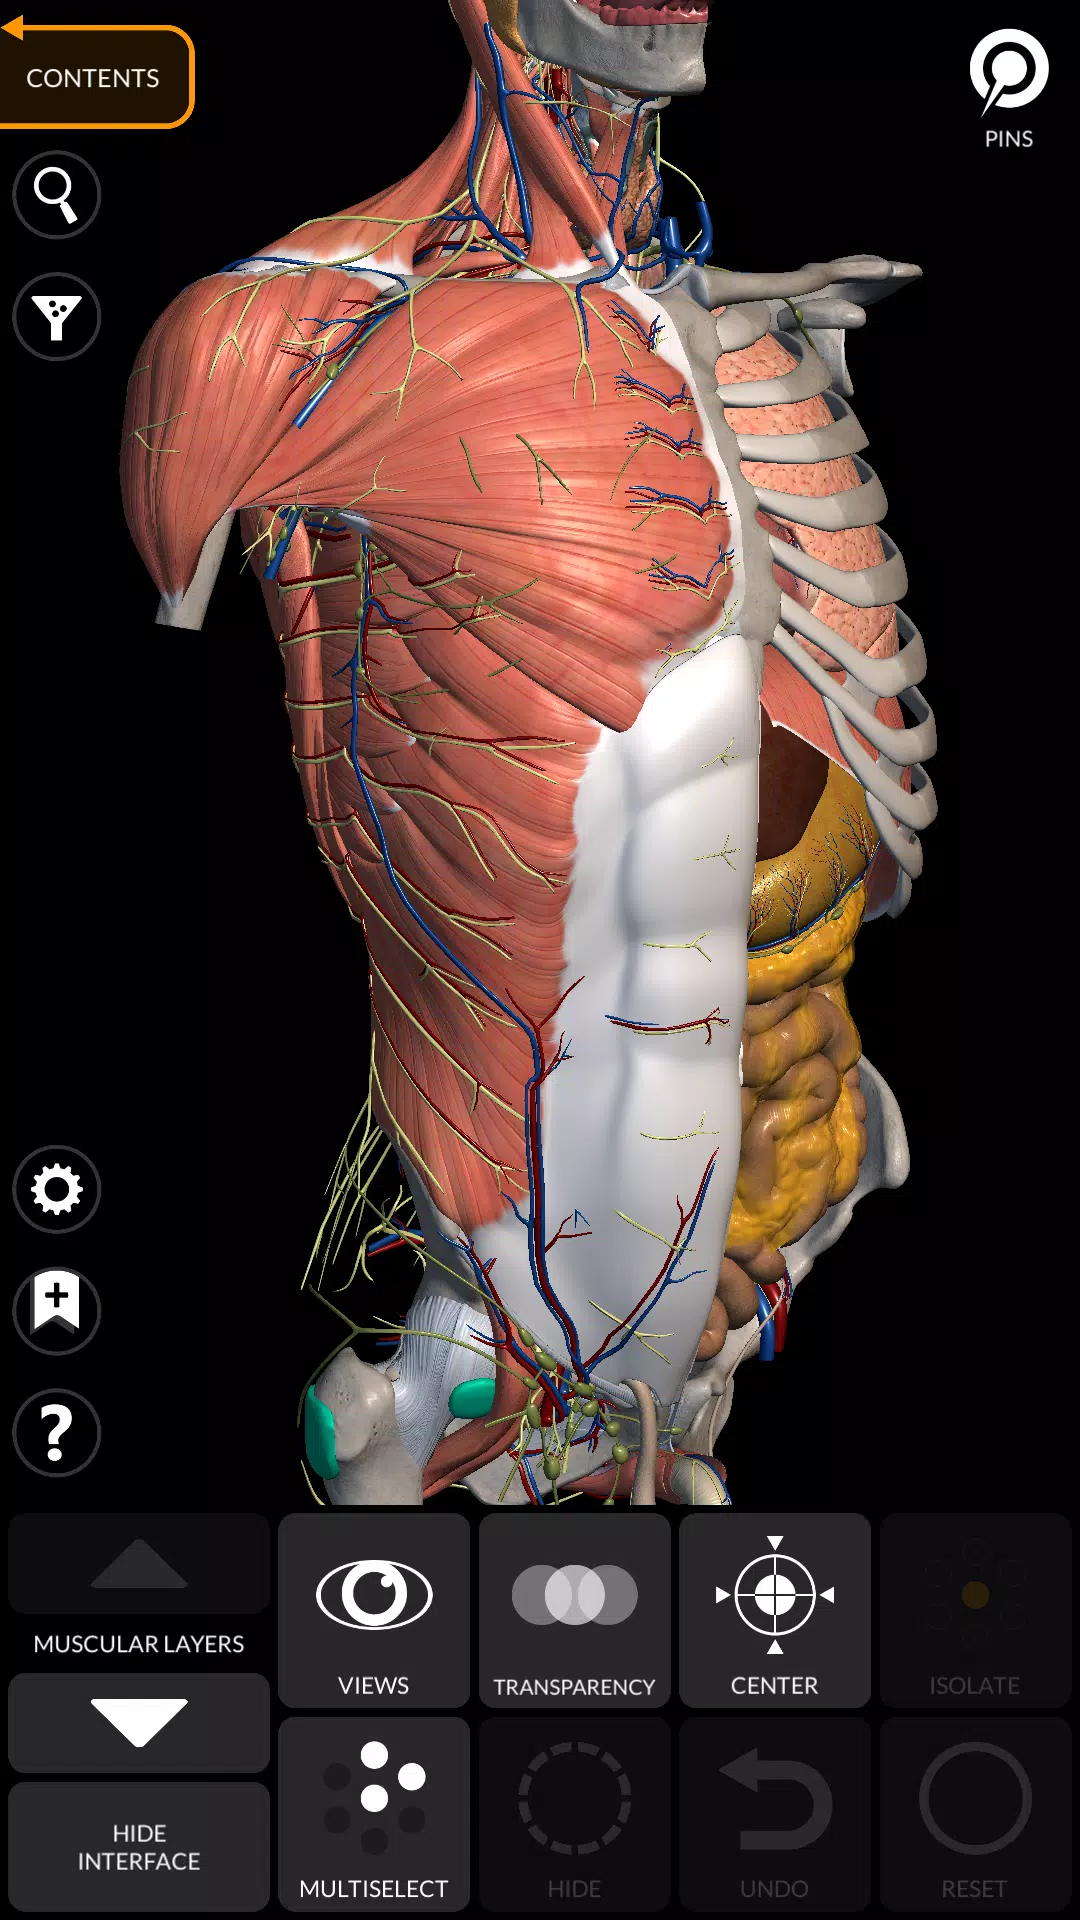

“ Anatomy 3D Atlas”通過其用戶友好和直觀的界面徹底改變了您研究人類解剖結構的方式。您可以從任何角度檢查每個解剖結構,這要歸功於高度紋理高達4K的質地的高度詳細的3D模型。該應用程序的組織按地區和預定義的觀點簡化了對單個部分或系統組以及不同器官之間的關係的研究。

- 心血管系統

- 通過選擇模型或引腳,相關的解剖術語顯示

Anatomy 3D Atlas應用截圖